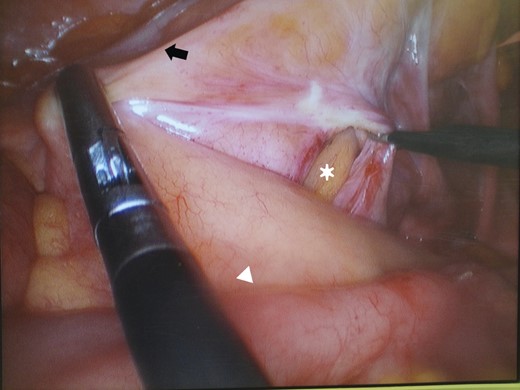

Contrast enhanced CT showing the transitional zone (white arrow) between dilated to collapsed loops in the left lower abdomen.

A laparoscopic approach was performed with the patient under general anaesthesia. A 10-mm port for camera was placed umbilicus by an open method. Two other 5-mm ports were placed for instruments in the right upper and lower abdomen. As tracing retrograde from the ileocecal junction, a loop of mid-ileum was incarcerated to ∼2-cm sized defect lateral to the sigmoid colon. First, trying the reduction of small bowel loop by atraumatic grasper gently, detachment of sigmoid lateral attachment was performed. Incarcerated bowel was released as soon as we detached a just little (Fig. 3). Approximately 15 cm of small bowel had been incarcerated in the defect and initially appeared congested but its colour and peristalsis improved rapidly. The hernia defect did not involve the medial aspect of the peritoneum on the sigmoid mesocolon and was confirmed no full-thickness defect. The defect was disappeared and changed to broad space easily from dissection of peritoneal attachment. There was no need to close the defect by intracoporeal suture laboriously. The operation was finished after confirmation of preventing recurrence. The postoperative course was uneventful and the patient was discharged 5 days postoperatively. The patient is free from recurrence.

After reducing the incarcerated ileum (white arrowhead), the defect (asterisk) in the lateral leaf of the sigmoid mesocolon (black arrow) is seen.